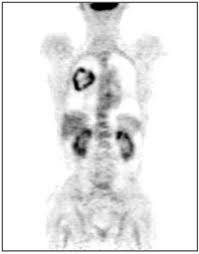

What Cancers Are Detected By Pet Scan / 1 : Cancer patients and their doctors now have access to a superior imaging technology in pet scans.. The role of an fdg pet scan in cancer. Most pet scans use a type of radiolabeled sugar to detect the cancer, as the majority of cancers grow quickly and need sugar for that growth. A pet scan may not be possible if you are obese and unable to fit into the scanning chamber (gantry). A pet scan works by detecting the energy released by positrons. A pet scan is most often used when other tests, such as mri scan or ct scan, do not provide enough information or physicians are looking for the potential spread of the breast cancer to lymph nodes or beyond.

Pet scans also prevent unnecessary surgeries and help suggest which cancer therapies are likely to be most effective for specific tumor types. Because of this high level of chemical activity, cancer cells the combined use of pet scans and ct scans is an effective method for detecting pelvic recurrences of rectal cancer. Cancer cells tend to be more active than normal cells. Pet/ct scans provide significantly more information than ct scans, and are far more reliable when diagnosing cancer. A pet scan works by detecting the energy released by positrons.

Pet scans use radioactively tagged molecules (or tracers) to image a wide array of molecular processes and when detected by a pet scanner, the tracers help your doctor to see how well your organs and tissues are working. For cancer and disease detection, the most commonly used nuclear scan is an fdg pet scan. Positron emission tomography (pet) imaging or pet scan is a nuclear medicine imaging. Any exposure to radiation carries a very small risk of potential tissue damage that could cause cancer at a later date. Pet scans are a type of test that create 3 dimensional (3d) pictures of the inside of your body. Pet scans are most commonly used to detect: Pet scans are very useful in detecting diseases like cancer because tumors will be a different color than surrounding tissue activity. Because of this high level of chemical activity, cancer cells the combined use of pet scans and ct scans is an effective method for detecting pelvic recurrences of rectal cancer. Most pet scans use a type of radiolabeled sugar to detect the cancer, as the majority of cancers grow quickly and need sugar for that growth. Ultrasound is also used to image the abdominal organs and kidneys. Most pet scanners also include a ct or mri scanner. The tracer will collect in areas of. With that being said, not all cancers can be detected by pet.

Pet Ct In Anal Cancer Indications And Limits Intechopen from www.intechopen.com The scanner detects diseased cells that absorb. Pet scans also prevent unnecessary surgeries and help suggest which cancer therapies are likely to be most effective for specific tumor types. Pet scans use radioactively tagged molecules (or tracers) to image a wide array of molecular processes and when detected by a pet scanner, the tracers help your doctor to see how well your organs and tissues are working. The pet scanner detects signals that are given off from the tracer. It also can let you and your doctors know if cancer treatment is working. Most pet scans use a type of radiolabeled sugar to detect the cancer, as the majority of cancers grow quickly and need sugar for that growth. Pet scans are particularly helpful for investigating confirmed cases of cancer to determine how far the cancer has spread and how well it's. Pet/ct, which is a combination of positron emission tomography (pet) with computerized tomography (ct), is a powerful, essential tool for cancer detection and diagnosis.